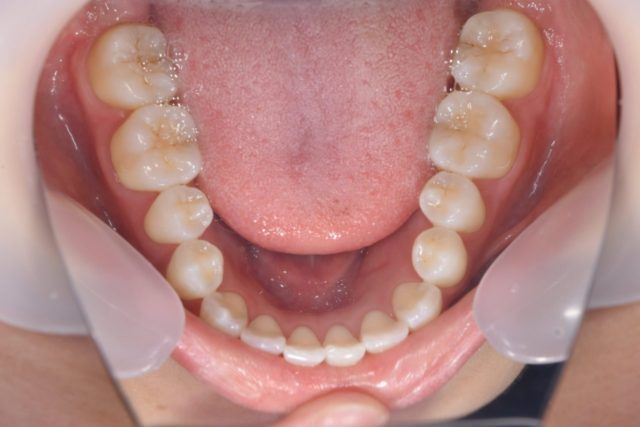

⑥お口を大きく開けて頂き、鏡で下顎の噛み合わせを写したお写真

下の歯の噛み合わせ部分や歯並びを診ることが出来ます。